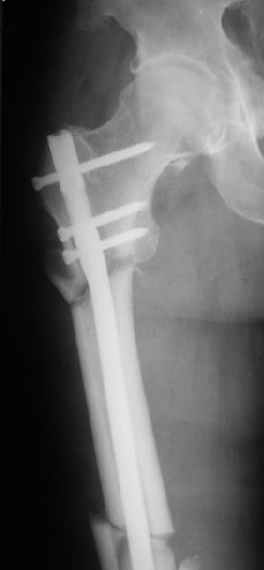

Картинка красивая, но на мой взгляд, не совсем оптимальная: Слишком медиально введён стержень - риск аваскулярного некроза головки бедра.

вариант межфрагментарного шинирования - зона достаточно простительная т.е. чрезвертельные переломы потенциально хорошо срастаются при любом

расположении сопредельных отломков- хорошая локальная васкуляризация. В приведённом случае я бы предпочёл принцип межфрагментарной компрессии (рекон/гамма нэйл 130- 135) принципу шинирования перелома.

Женя, эта картинка показывает не оптимальное лечение вертельных переломов в моем представлении, а особенности дизайна упомяутого фиксатора.

В частности, его возможности при фиксации переломов проксимального отдела бедра - в сравнении с другими, имеюшими лишь по одному статическому и динамическому отверстию и с кондуктором для введения 2 винтов.

Это было года 2,5 назад, мы тогда еще уточняли возможности шинирования с угловой стабильностью гвоздем с поперечным расположением винтов при переломах проксимального отдела бедра. Пациенту не пришлось приобретать намного более дорогой рекон или проксимальный гвоздь. В приложении еще несколько примеров применения того гвоздя при высоких переломах бедра, в том числе с более латеральной точкой входа. Гвоздь изгибаем для этого.